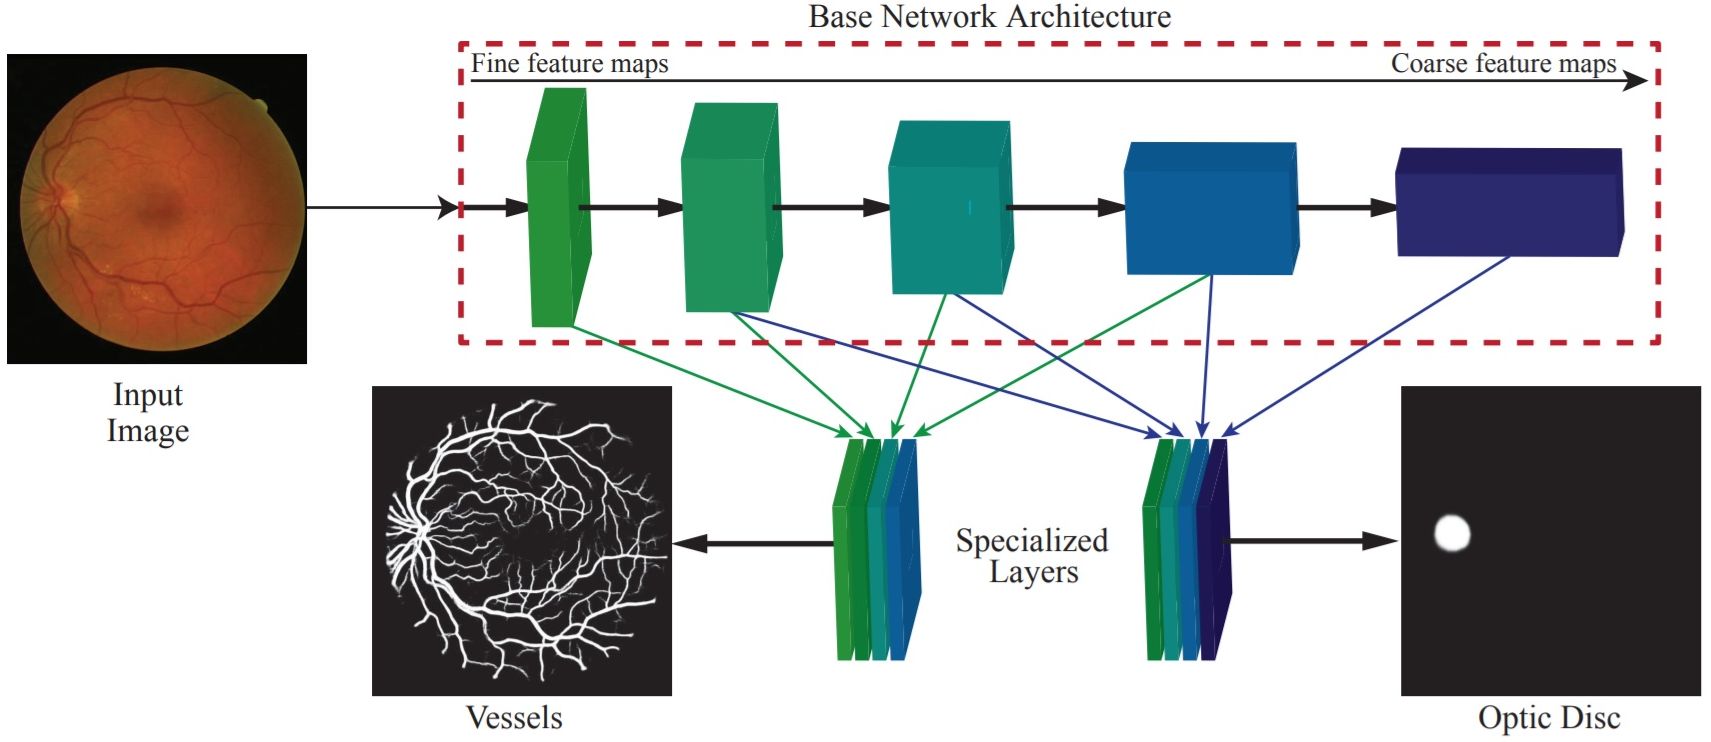

DRIU [7], the basis of the model presented here, was intended to segment the optical disc and blood vessels of the eye. The Fully Convolutional Network (FCN) used by DRIU has side outputs with supervision at different convolution stages[11]. The output is obtained by combining the multi scale side outputs.

The deep learning model used [11] is based on the Deep Retinal Image Understanding (DRIU) network [7], a model which performs the segmentation of the eye’s blood vessels and optical disc. An overview of DRIU is presented in Figure 3.3. After extracting side features, DRIU builds special layers for the segmentation of arteries (left) and optical disc segmentation (right). Using convolutions, activation functions and max poolings, the architecture is itself inspired from VGG-16 [30]. As such, the base network is VGG-16 pretrained with Imagenet [87] and is made of convolutional stages which activate at same feature map resolution and are separated by pooling layers. At deeper levels, the information is more general and the learned features are closer to semantics [11]. Being fine structures, the blood vessels benefit from the less deep layers, where the information is more granular. In the same time, the optic disc is advantaged by the deeper layers and more general features. Thus, DRIU uses several side outputs (convolutional layers connected at the end of a specific convolutional stage of the base network) specialized in different feature levels and the output is obtained by scaling and combining the side outputs.